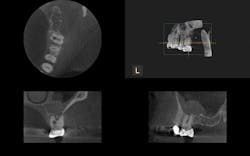

Radiolucency seen on the first molar, and the second molar demonstrates major bone loss in furcation due to a fractured root. The axial view depicts a resorptive defect along the actual fracture line.

The buccal and palatal plates of bone are intact here, but there is tremendous infection in the furcation.

CBCT shows a missed MB2 on the last tooth, the second molar.

The CBCT scan reveals palatal root resorption.